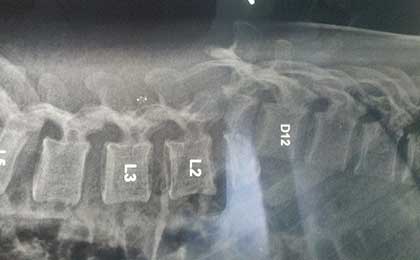

L5 S1 DEG LYSIS LISTHESIS

pre op xray 1